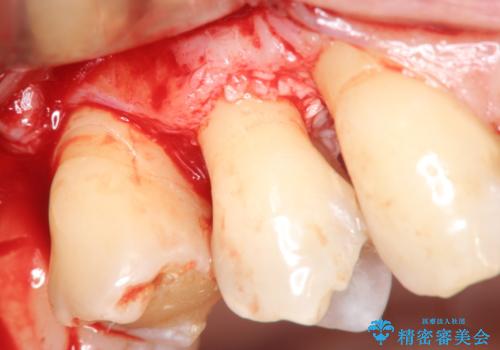

部分矯正を含む 歯周病治療 (再生治療・歯周ポケット除去・MTM・連結補綴)

検査の結果、強い歯ぎしりによる歯の周囲の骨の吸収が認められたため歯槽骨の再生・歯周ポケットの除去・力に対抗する連結補綴・補綴前処置としての小矯正を計画します。

特定の歯に強く力がかかりまた歯周病により臨床歯根が短くなっているような場合、歯の動揺を抑えるため連結補綴が検討されます。

歯の動揺が続くとより周囲の骨を失い最終的には歯を喪失してしまう可能性が高くなってしまうためです。

今回連結補綴を行うにあたり、歯周病の問題を解決するために再生療法・歯周ポケット除去手術を、またより歯の神経を保存し力に対抗できる環境を整えるために小矯正を行い精度の高いメタルボンドクラウンを製作することができました。